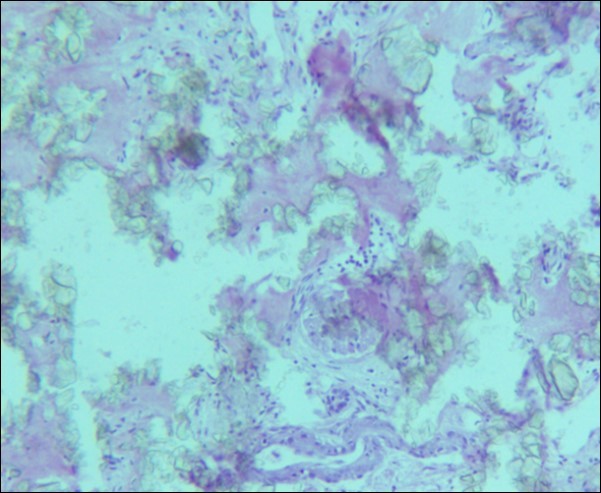

A 30 years old male, resident of Lahore was admitted for opinion regarding the necessity for regular hemodialysis after rejection of second renal transplant. Family history was suggestive of hereditary disease as two of his sisters had died of nephrocalcinosis leading to chronic renal failure at the age of 4 years. Consanguineous marriages in past many generations were also reported. Three cousins of the patient had recurrent stones with normal kidney functions. His past history revealed retention of urine at the age of 5 years due to stone in urethra. Patient presented again after 20 years in 2008 with retention of urine which was relieved by catheterization. Renal ultrasound and X ray KUB reported normal kidneys in both instances. Work up for stone formation was not undertaken at that time. The patient was put on hemodialysis and was planned for transplant which was undertaken in May 2009. After one month, follow up tests revealed Serum Creatinine to be 2.0 mg/dL. Renal Biopsy done in Sep 2009 revealed rejection of transplant. Hemodialysis was started and a second transplant was contemplated. Hemodialysis continued for 2 years till Dec 2011 when second transplant was carried out. A repeat renal biopsy was indicated for increasing serum creatinine. Again transplant rejection was evident on histology. Further investigations revealed Urinary oxalate excretion exceeding 40 mg/day (30 mg Oxalate/gram creatinine). His Blood investigations at the time bone marrow studies revealed bicytopenia with a Haemoglobin of 7.8g/dl, White blood cell count of 5.8 x 109/l; Platelet count of 120 x 109/l. Serum Creatinine was 3.6mg/dl. An attempt to correct the cytopenias by iron, vitamin B12 and folic acid supplements met with failure. No response to anemia could be elicited by adding erythropoietin to the treatment regimen. Renal and bone marrow biopsy were undertaken. Renal biopsy of the patient revealed crystals of calcium oxalate in the tubules (Figure 1). The same crystals were also visualized in bone marrow aspirate (Figure 2a and Figure 2b) and trephine biopsy (Figure 3).

Figure 1.Photomicrograph of renal tissue from case I with a preserved glomerulus and clusters of oxalate crystals in the tubules.